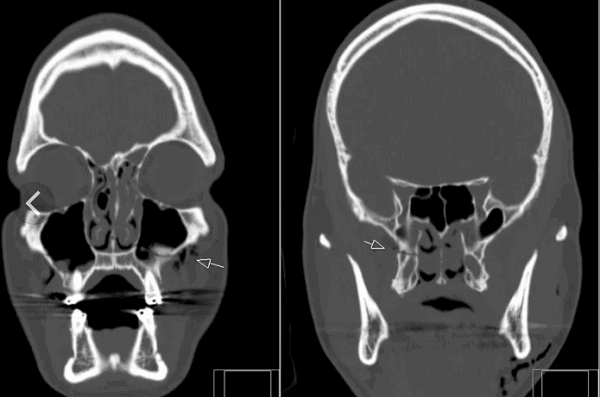

(Слева) КТ, аксиальный срез: отрывной перелом нижнего края правого мыщелка затылочной кости, фрагмент смещен медиально.

(Справа) На фронтальном КТ-срезе у этого же пациента также определяется небольшой отрывной перелом нижнего края правого мыщелка затылочной кости. Также здесь виден косой перелом правой боковой массы С3.